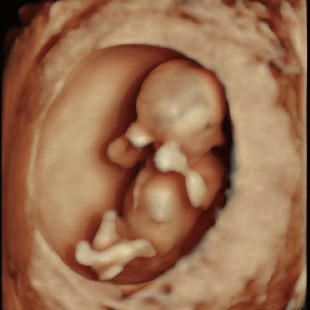

通常の妊婦健診で行う超音波検査では、主に胎児発育(推定体重)、羊水の量、胎児の向きを確認しています。一方で健診の限られた時間内では、胎児を詳細かつ系統的に評価することが難しい場合があります。当院で行っている胎児超音波スクリーニングとは、高性能な超音波検査機器を用いて胎児の発育や形態(からだの構造)をより詳しく観察し、胎児の状態を丁寧に評価する検査です。 出産前に赤ちゃんの状態をより詳しく知りたいという患者さんのご希望にお応えするため、当院では超音波検査士*および超音波専門医・指導医**が胎児超音波スクリーニングを担当します。

Voluson Expert 22®(GEHealthcare)という産婦人科領域におけるハイエンド超音波診断装置を使用しています。 従来機種と比べ、より高精細な画像描出性能と高度な解析機能を備えており、 胎児の発育や形態をより詳細に観察することが可能です。